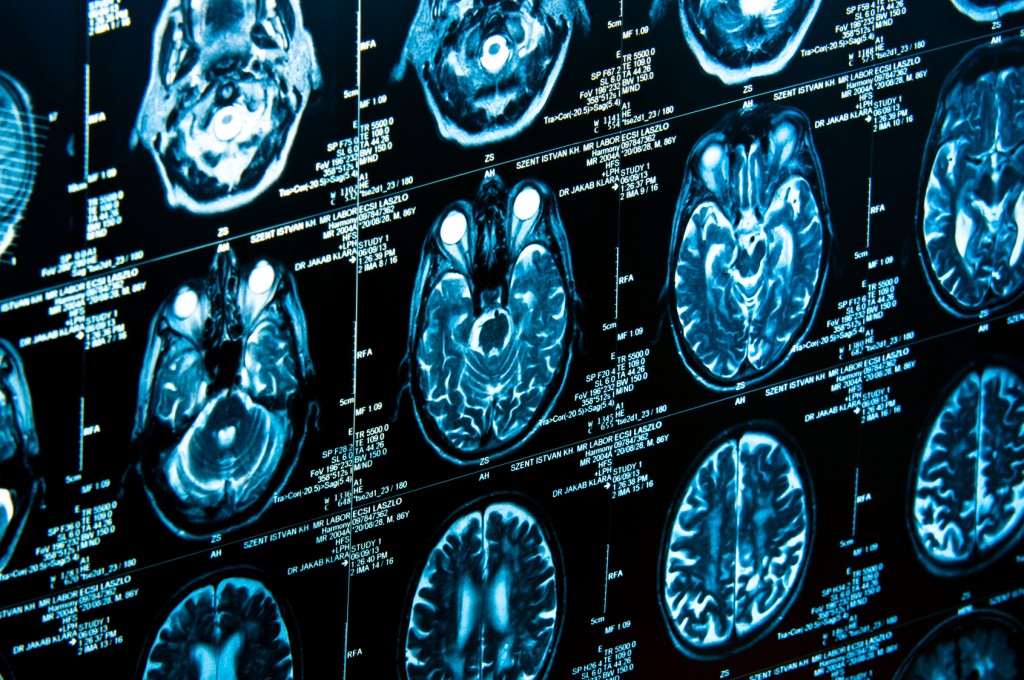

In the study, neuroscientists used functional magnetic resonance imaging (fMRI) to examine the brain scans of patients as they looked at angry faces and neutral faces. The patients whose brain scans showed a greater difference in the high-level visual processing areas during the face-response task showed the most improvement after therapy.